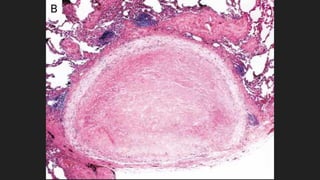

Lesiones pequeñas de

criptococosis cutánea

A) Lesión ulcerada de piel en paciente HIV

B) Lesión nodular de piel causada por C.

neoformans.

A B